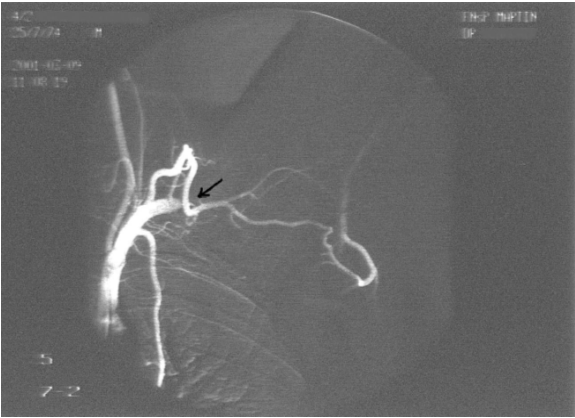

A 26-year-old left-handed healthy man presented with a three month history of repeated bilateral chest pain. Six months previously, he started heavy muscular activity of upper limbs (work out at a gym). Two months before he had been examined by his pulmonologist because chest X-ray revealed bilateral small effusion and tuberculin test had been positive. The patient started treatment as suspected tuberculous pleuritis and beside antituberculous drugs he used corticoids too. Despite treatment, difficulties remained and the patient was remitted to our clinic. On examination, there was no edema of the left arm, only prominent superficial veins on arm and left part of chest. On auscultation of the lungs, breath sounds were weakened bilaterally. Chest radiography revealed small pleural effusion. Electrocardiography and echocardiography were normal. Suspected pulmonary embolism was confirmed by computed tomography. DVT in lower limb was excluded by compression ultrasonography. Because the patient had prominent superficial veins on arm and left part of chest, we suspected left subclavian vein thrombosis, which was established by venography (Figure 1). Aortography revealed aneurysm of left subclavian artery (Figure 2) and also confirmed left thoracic outlet syndrome due to adherent first and second ribs (Figure 3), interruption of flow in left subclavian artery in abduction of left upper limb and appropriate flow in left subclavian artery in adduction of left upper limb (Figure 4). Patient was administered low molecular weight heparin as initial step, followed by the acenocoumarol therapy. A thrombophilia screen revealed prothrombin 20210A mutation, which was detected by polymerase chain reaction.

Figure 2: Aortography of aortic arch: Aneurysm of left subclavian artery is marked by the arrow.

Figure 3: Aortography showed, interuption of flow in left subclavian artery in abduction of left upper limb marked by the arrow.